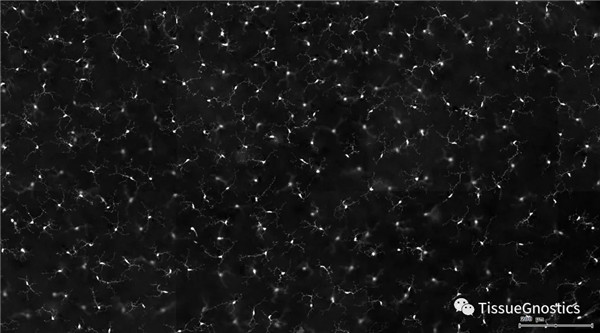

單通道灰階圖(↑:FITC,↓:Texa Red)

根據(jù)染色強(qiáng)度,染色面積,細(xì)胞形態(tài)學(xué),利用正反向回溯功能和設(shè)門圈選Gating,排除雜質(zhì),細(xì)胞碎片,黏連細(xì)胞(綠色框線標(biāo)記),獲得神經(jīng)元胞體,(粉色框線標(biāo)記),并將胞體按照面積分為兩類(散點(diǎn)圖)。

由于該視網(wǎng)膜樣本是標(biāo)記的小膠質(zhì)細(xì)胞,根據(jù)面積將神經(jīng)胞體分為兩類(Small bodycell,Big bodycell),反向回溯Big bodycell中的細(xì)胞后,應(yīng)用Input Gate功能篩選短粗的神經(jīng)纖維,作為激活態(tài)的小膠質(zhì)細(xì)胞。